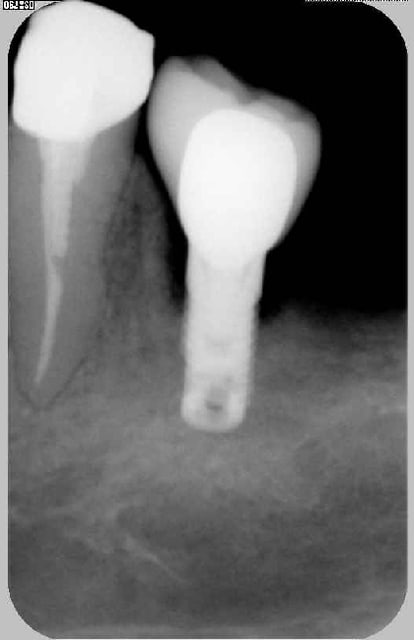

j'avais interprété les photos dans l'ordre suivant:

-implant à 3-4 mois

- implant + couronne quelques mois après la mise en charge

alors qu'en fait c'est l'implant le jour de la pose et la couronne le jour de sa mise en place .

je pensais donc, que la destruction osseuse était vraisemblablement dûe à un problème occlusal alors qu'en fait, en remettant les photos dans l'ordre, on peut rejeter cette hypothèse car l'os s'est reformé grâce à la persistance d'une trame collagénique et à la stimulation mécanique (avec élimination maximale bactérienne dans la zone)

ci-dessous les photos dans l'ordre où je les avais classé: